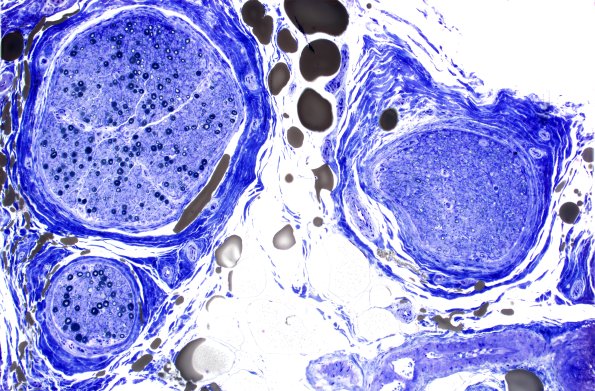

3E1-3 Toluidine-blue stained sections showed mild crush artifact and patchy loss of both large and small axons. Clusters of small axons as well as axons with myelin sheaths which are thin for axonal caliber, both indicative of a cycle of degeneration/regeneration, are present. One fascicle shows nearly complete replacement by thinly myelinated axons.